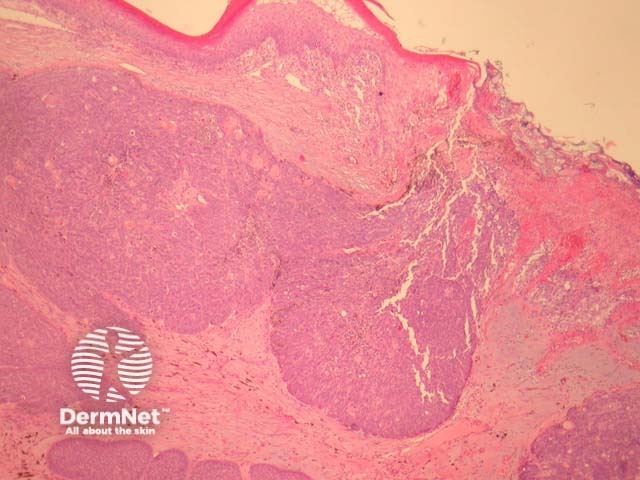

Sections through melanocytic matricoma show a well-circumscribed dermal tumour which may encroach and erode the overlying epidermis (figure 1). There is heavy melanin deposition. The tumour is made up of basaloid cells with some nuclear pleomorphism and conspicuous mitotic activity. Intermixed with these epithelial cells are a population of dendritic melanocytes (figures 1-4). There is focal “ghost cell” keratinisation (figures 5, 6).

Figure 1